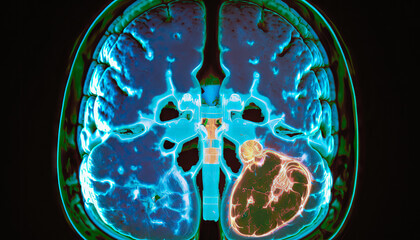

오늘은 여러분들께 뇌종양 같은 말로 뇌암의 증상 그리고 치료 방법에 대해서 알아보도록 하겠습니다.

뇌종양 증상

뇌종양은 크기가 커질수록 뇌를 압박하면서 악성으로 변하게 됩니다.